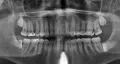

В течение нескольких месяцев у меня иногда болел зуб, боль была не сильной и проходила самостоятельно, при жевании на стороне зуба болезненность не отмечалась. Когда обратилась к стоматологу, он определил, что больной зуб четвертый сверху, сделал снимок, прочистил каналы и поставил мышьяк, в итоге он удалил мне нерв. Прочитала в инете, что нерв удаляют только при крайних случаях, когда боль невыносимая или зуб темнеет.

Действия врача абсолютно верные, у зуба диагноз пульпит, и его необходимо было депульпировать, в противном случае вы могли заработать себе хроническое воспаление (периодонтит).